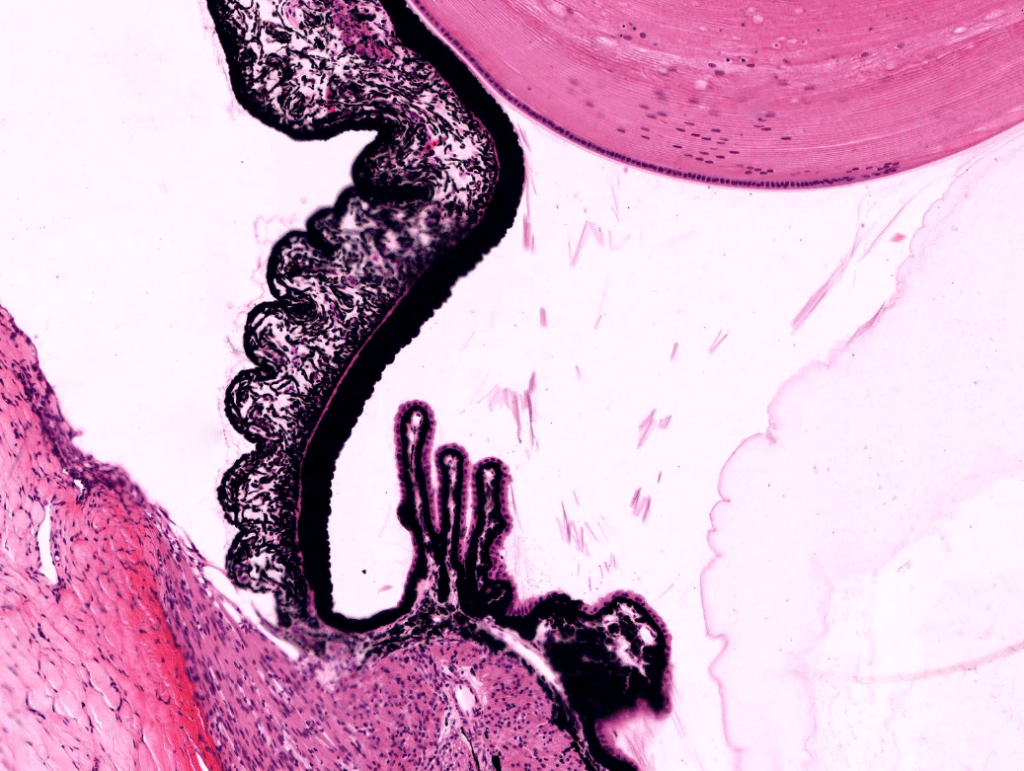

CUERPO CILIAR